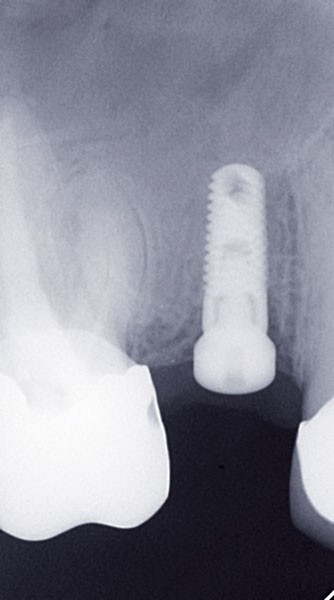

Le praticien s’assurera de la bonne intégration de l’implant avant la prise d’empreinte après examen clinique et radiographique (fig. 1).